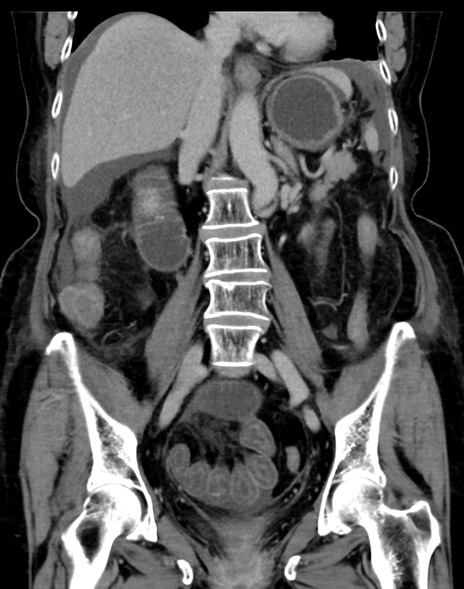

症例13 CT(冠状断像)1日半後